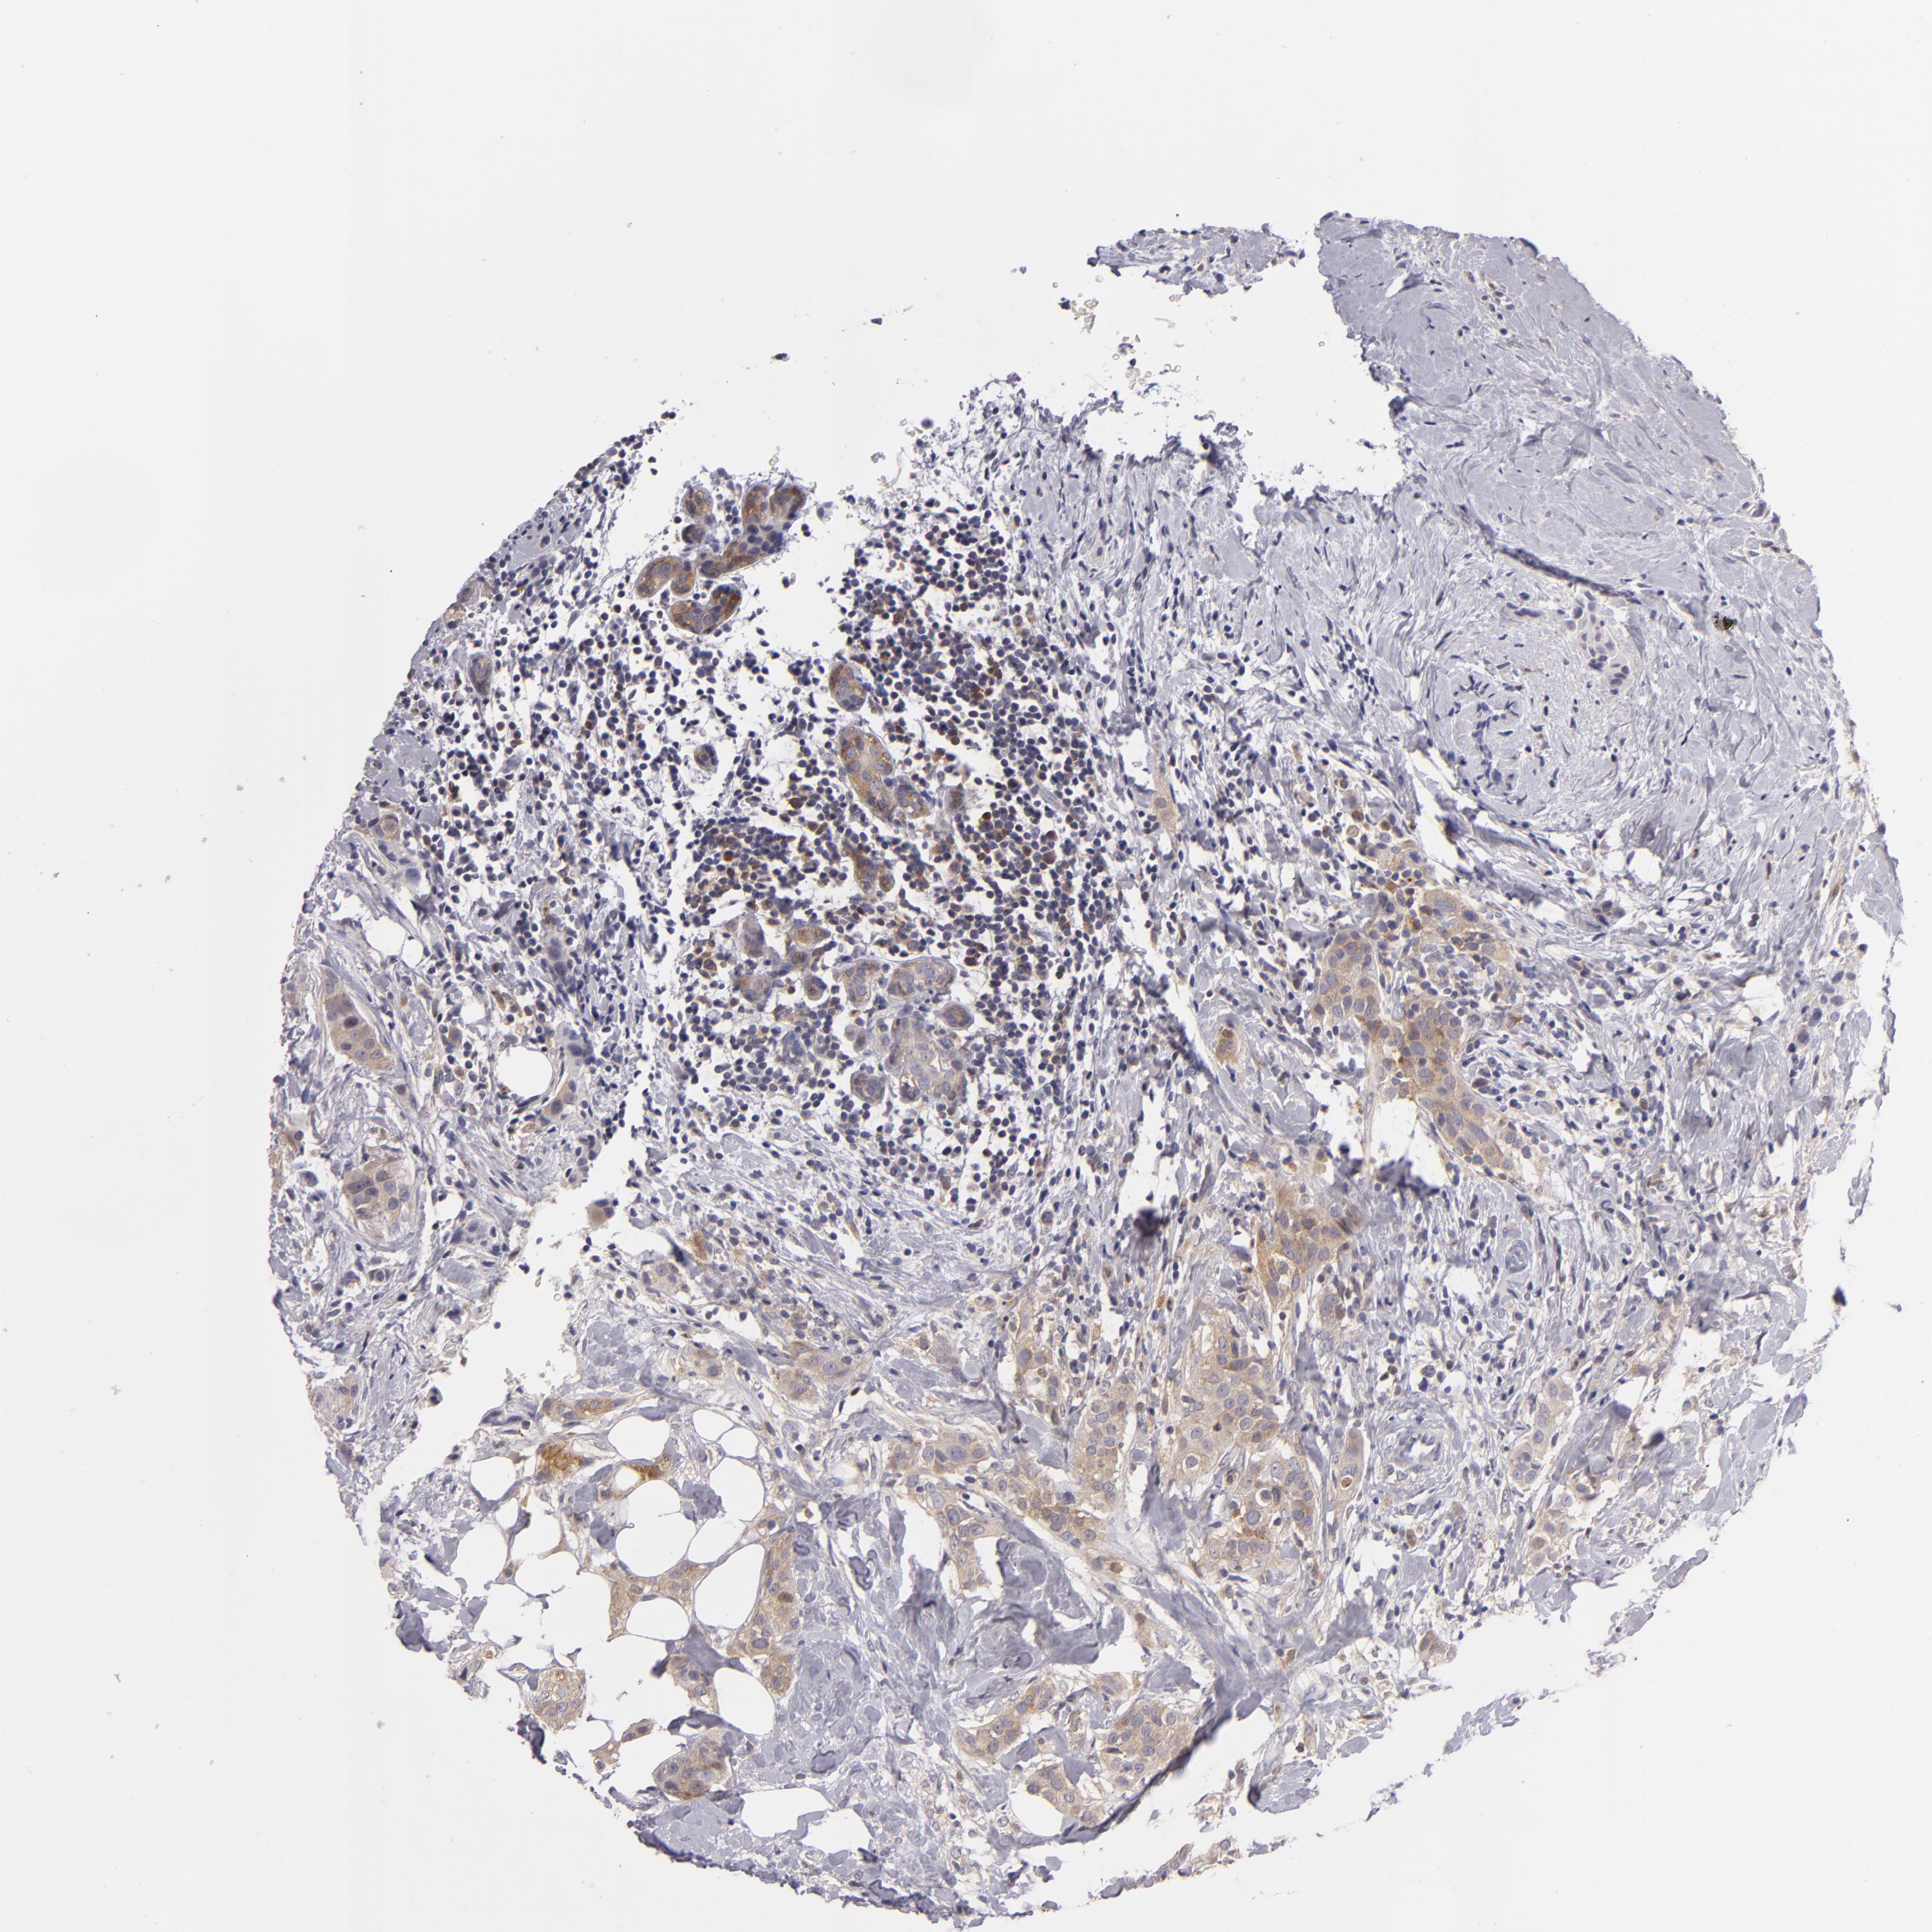

BRCA TCGA BRCA VALIDATION PROTEIN EXPRESSION

ANTIBODIES

AND

VALIDATION